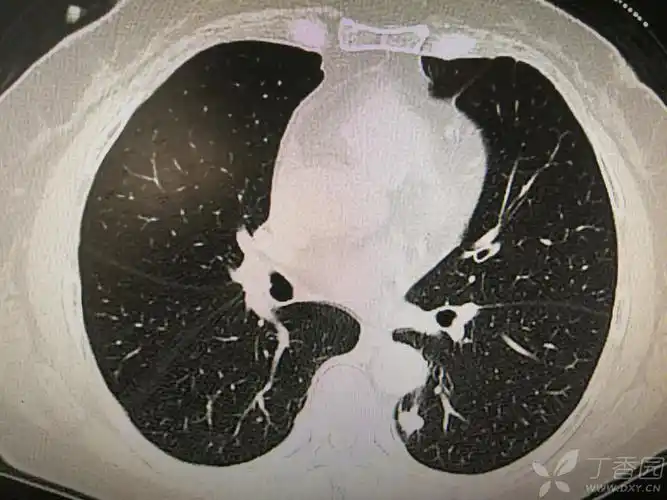

左下肺背段见分叶状结节影,会是什么?